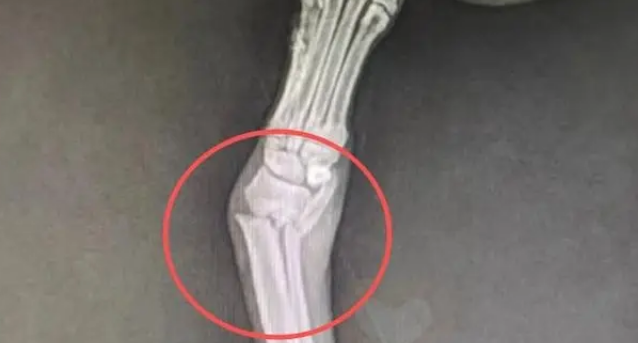

我这才看清它的伤势——右前腿肿得不成样子,显然是骨折了。当我的手指无意中触碰到它的伤腿时,它浑身一颤,却依然坚持着给孩子们喂奶的姿势。后来,从附近的村民口中,我得知了这场悲剧的始末——这些小狗刚出生就被主人扔进了河里,狗妈妈是自己跳下去,一只一只把孩子救上来的,为了救孩子,它生生摔断了腿。

我没有犹豫,立刻将它们全家送往了最近的宠物医院,检查结果像一记重锤,敲得我心口发疼。七只小狗因为长时间浸泡在河水中,全部感染了细菌,医生说随时可能发展成败血症,狗妈妈的情况更糟,右前腿严重骨折,必须立即手术,否则将永久残疾。